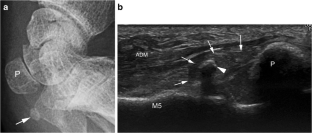

Fig. 2